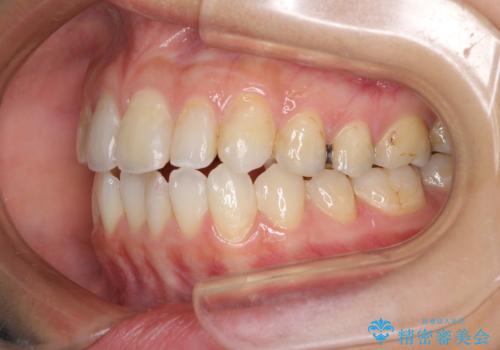

後戻りを治したい 骨格的なズレの大きい方のインビザライン矯正

- 中学生の時に矯正治療をしたものの、後戻りを気にして来院された患者様です。

骨格的に下顎が右側に変位しているため、左右の咬み合わせを理想的なものに改善することはできませんが、インビザラインにて歯列を整えることとしました。

骨格的なズレによる左右差は改善できませんでしたが、上下の正中を極力合わせるようにすることができました。